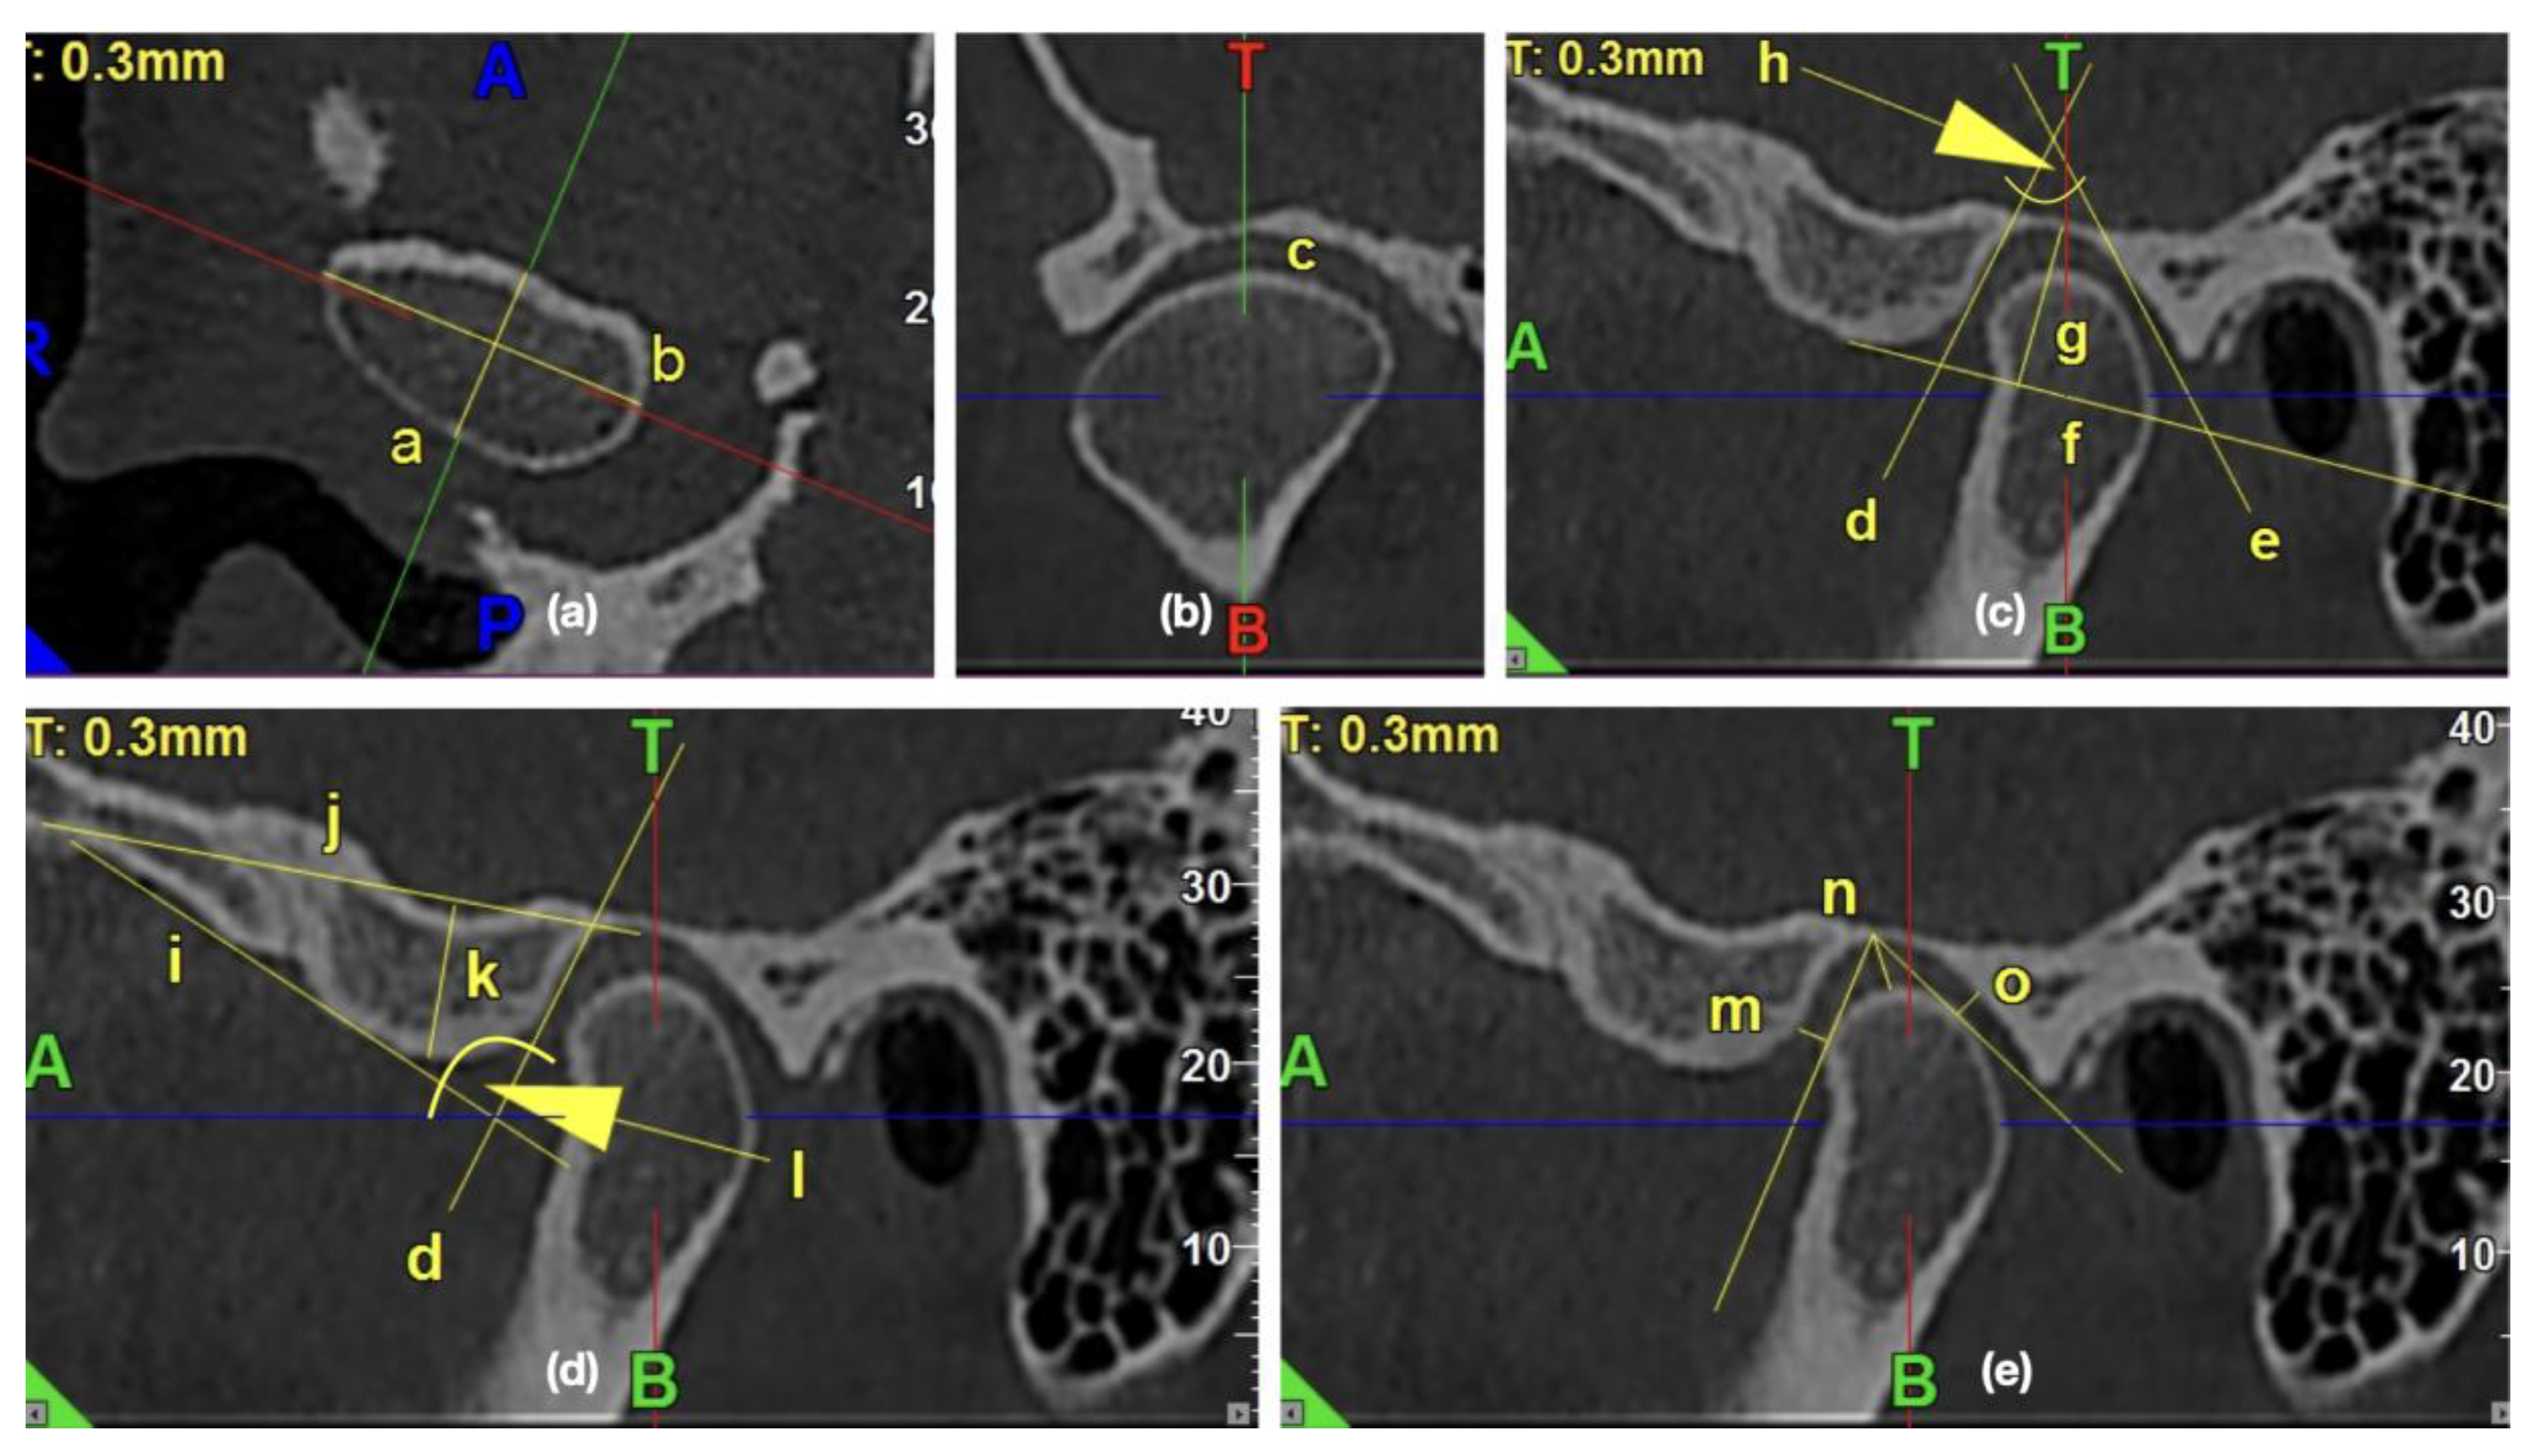

In the CBCT images, the presence of the osteoarthritic changes was assessed. The radiographic symptoms of degenerative joint disease are [20,24,25,26,27,28,29] as follows: flattening of the convex condylar head; erosion (the area of reduced density within the cortex and subcortical bone); osteophytes (bone outgrowths on the surface of the condyles); sclerosis (increased density of the cortical plate or bone tissue under the cortical plate); pseudocysts (osteolytic, well delimited, localized in the subcortical area, the cortical layer does not become destroyed in its course). Figure 1 presents the exemplary osteoarthritic changes found in the TMJ CBCT scans.

Figure 1. The exemplary osteoarthritic changes found in the temporomandibular joints (TMJ) cone beam computed tomography (CBCT) scans: (a,b) Articular surface flattening; (c) Erosion; (d) Osteophyte; (e) Subcortical sclerosis; (f) Generalized sclerosis; (g,h) Subcortical cyst.